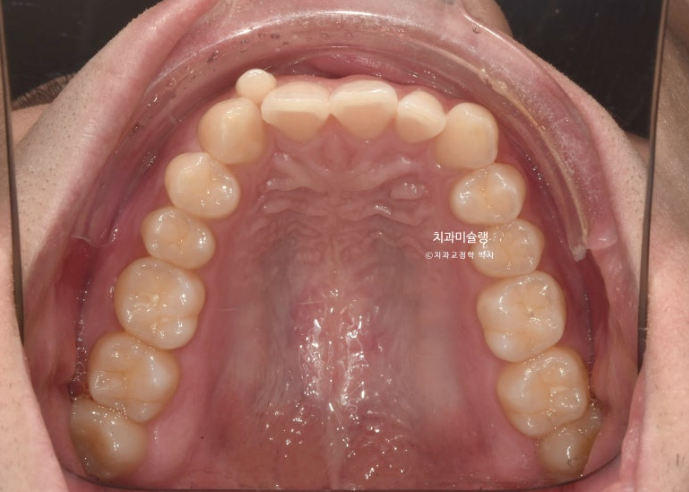

왜소치 덧니는 제자리로 잘 들어왔고 배열은 좋습니다.

이제 왜소치 무삭제 라미네이트를 할 차례입니다.

사선으로 마모된 앞니도 레진으로 끝단 모양을 회복하기로 합니다.

25.10~25.11

차례대로 교정 완료 직후 - 무삭제 라미네이트 부착 후 - 앞니 끝단 레진 치료 후 사진 입니다.